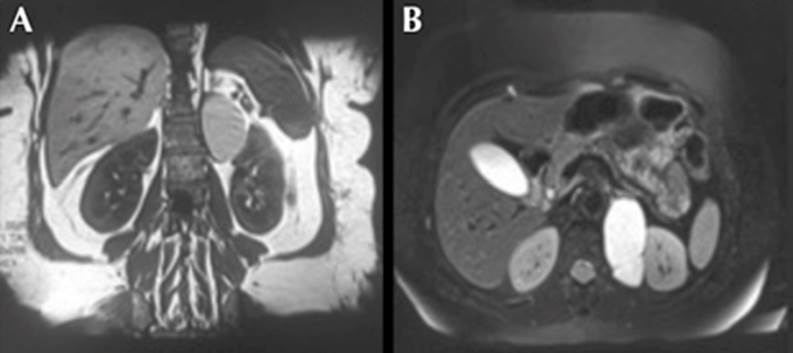

La resonancia magnética en secuencia T2 mostró una masa retroperitoneal adyacente a la parte interna del riñón, que desplazaba la glándula suprarrenal izquierda, de 38 x 67 mm de diámetro en corte axial. En secuencia T1 se comportó de manera hiperintensa, pero no se observó reforzamiento con el paso del medio de contraste, que también fue sugerente de un quiste (Figura 2).

Figura 2 Resonancia magnética. Cortes coronal (A) y axial (B), este último con imagen hiperintensa, pero sin reforzamiento con el paso del medio de contraste.

La resonancia magnética y la tomografía computada son estudios fundamentales para establecer el diagnóstico etiológico de las lesiones. En nuestro caso, la urografía por tomografía computada mostró una imagen hipointensa compatible con una masa sólida retroperitoneal; sin embargo, la resonancia magnética reveló una lesión quística, con líquido de alta proteína, característica de una imagen hiperintensa.5